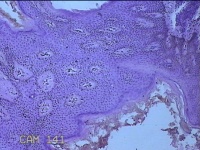

右侧头部息肉结节

性别

男

年龄

39岁

临床诊断

头皮良性肿瘤

一般病史

发现右侧头部息肉结节20余年。

标本名称

右侧头部息肉组织

大体所见

灰白暗红色组织1.2x1x0.8cm一块,表面带梭形皮肤1.2x0.8cm,皮下见结节1.2x0.9x0.3cm一个,切开结节呈实性,切面灰白暗红色,质软。